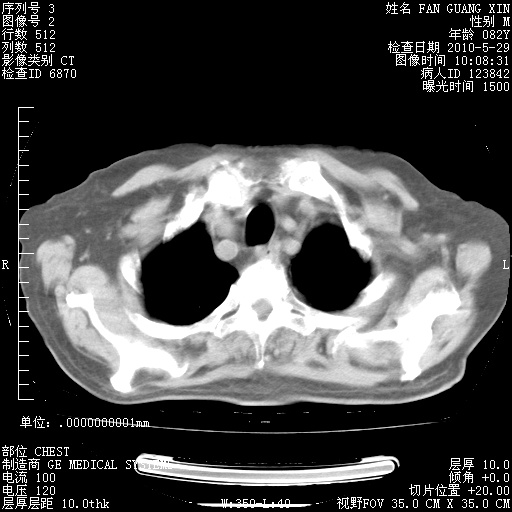

再治疗10天后的肺部CT